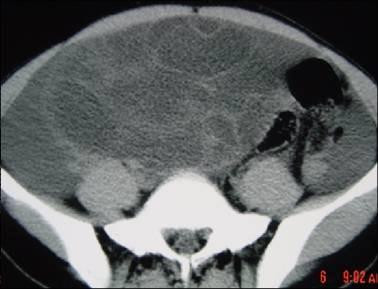

问题 40岁女性患者,下腹部隐痛、腹胀一年余,B超检查提示盆腔包块,行CT检查,如图,你认为最可能的答案是 ( )

选项 A、卵巢囊腺癌 B、卵巢浆液性囊腺瘤 C、卵巢囊肿 D、卵巢囊腺瘤 E、卵巢畸胎瘤

答案 D